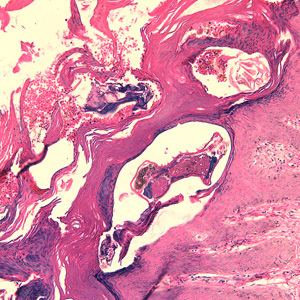

Case #244 – January, 2009

An 80-year-old resident of a long-term care facility presented with a skin condition manifesting as thick crusts over the skin accompanied by slight itching. The patient was originally treated for impetigo, with no resolution, and was ultimately admitted to the hospital for further testing. A skin biopsy was performed. The specimen was sectioned, stained with hematoxylin and eosin (H&E) and sent to a dermatopathologist for diagnostic assistance. Figures A–D show what was observed in the stained sections. Figures A and B were taken at 200x magnification. Figures C and D represent the same fields, respectively, taken at 400x magnification. What is your diagnosis? Based on what criteria?

Figure A